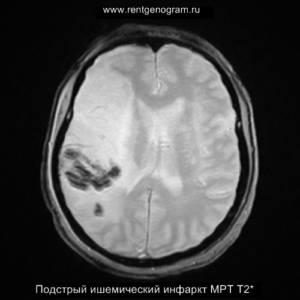

- подострая фаза (с 24 часов до 6 недель – накопление контрастного вещества)

Подострая фаза (24 часа — 6 недель)

На подостром этапе происходит разрушение гематоэнцефалического барьера, что приводит к вазогенному отеку, увеличивая объем ишемического инфаркта, возникновение масс-эффекта и возможного вклинения в случае обширного поражения (например, вклинение поясной извилины под фалькс или миндалин мозжечка в большое затылочное отверстие).

Когда в мозговых артериях происходит реканализация кровотока, это может привести к образованию геморрагических пропитываний и кровоизлияний («красный компонент» ишемического инфаркта), что будет отображаться на МРТ как ↑ на Т1 и Т2*, а на КТ — как участки с гетерогенной повышенной плотностью. На более поздних этапах подострой стадии наблюдается нормализация ранее повышенных показателей DWI и ADC, известная как «псевдонормализация» диффузии.